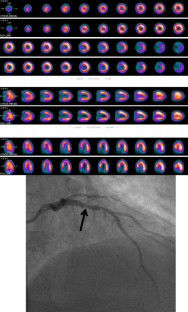

Fig. 1

Fig. 2